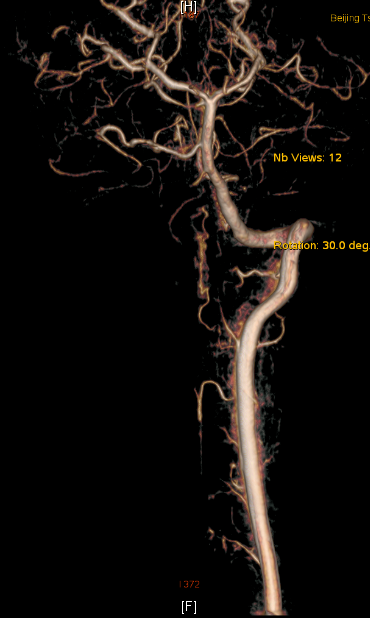

图1:术前MRI提示延髓高颈髓异常出血信号影(蓝色箭头指示)

神经外科王贵怀主任经过认真仔细的评估后,决定进行血肿清除和畸形血管切除术,再造脊髓髓内的血流。术后由神经外科神经介入专家苏伟医师给予复查血管造影,显示畸形血管基本全切,症状明显好转,住院2周已能下地自主活动,姑娘愁苦的脸上终于露出了笑容。